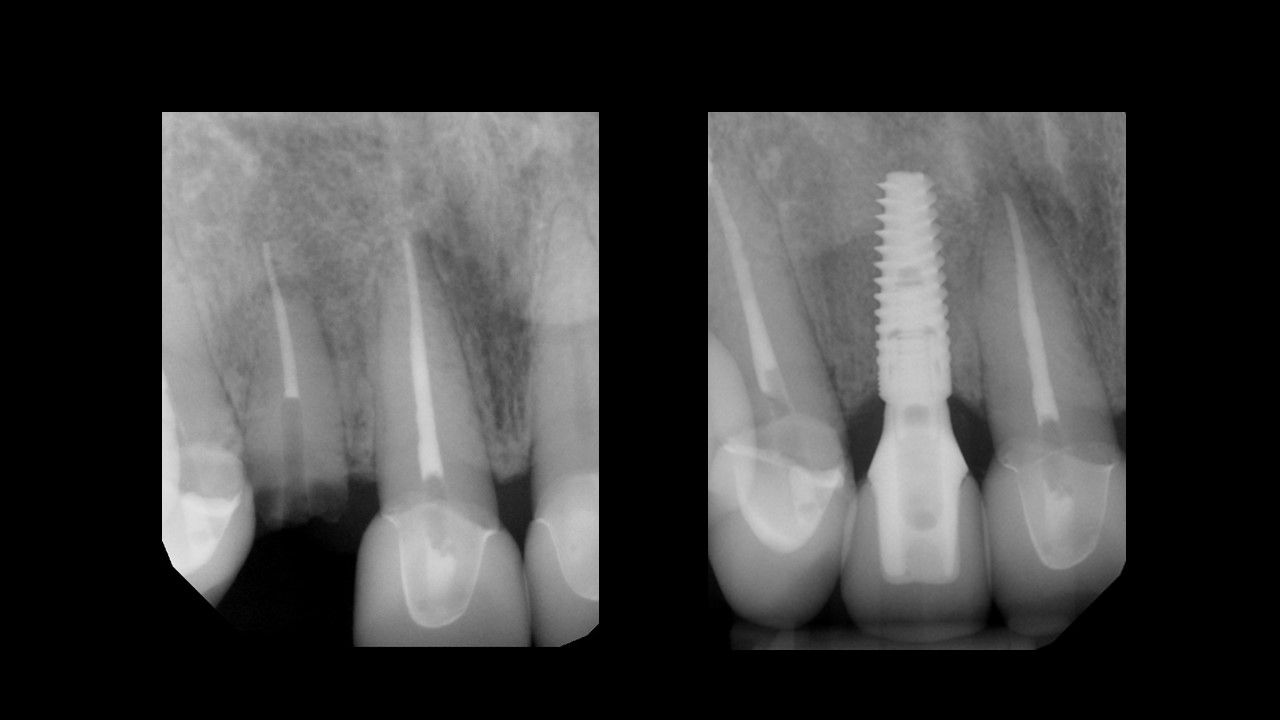

En utilisant un enseignement basé sur les procédures1, ce niveau aidera le clinicien à évoluer vers des concepts chirurgicaux et prothétiques plus avancés grâce au traitement de cas d’implants antérieurs à dent unique.

Tout au long de ce niveau, les cas couvrent des sujets tels que : Évaluation de l’os buccal et apical pour une implantation immédiate, Greffe autour d’implants immédiats (technique de la double zone), Définir l’orientation de l’implant – Les règles de six, Évaluer la stabilité primaire pour une mise en charge immédiate, Options et conceptions de piliers CAO/FAO. À la fin de ce niveau, les participants comprendront comment placer et restaurer un implant à dent unique dans la zone antérieure. Les participants sont invités à poursuivre leur formation au niveau 4, qui se concentrera sur les cas d’implants multiples.